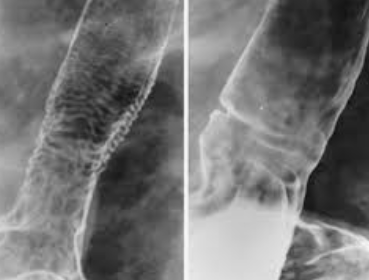

4. 바륨 삼킴(식도): 이 검사는 삼킴의 특성을 확인하고 식도가 좁아지거나 다른 구조적 이상이 있는지 확인합니다.